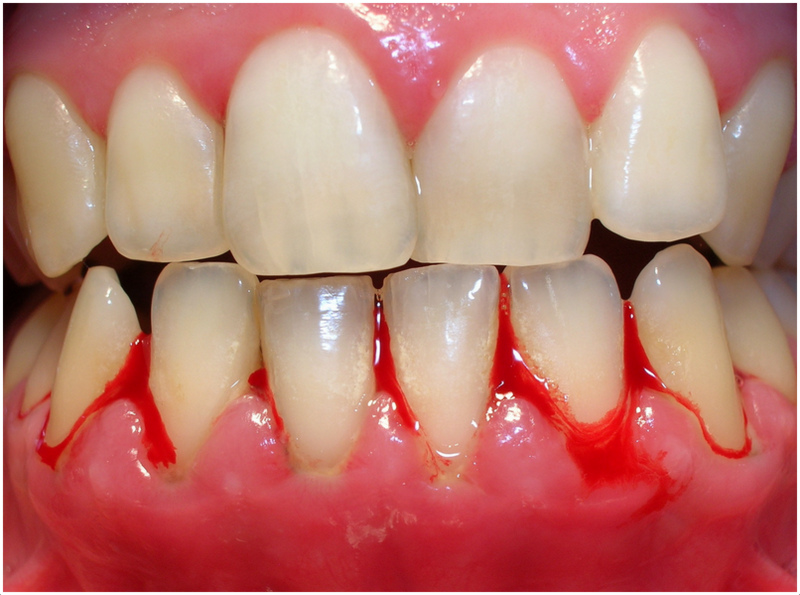

در اینجا یک روش است که کمک می‌کند خونریزی لثه

دندانپزشک همچنین نکاتی را به شما آموزش میدهد که میتوانید با رعایت…